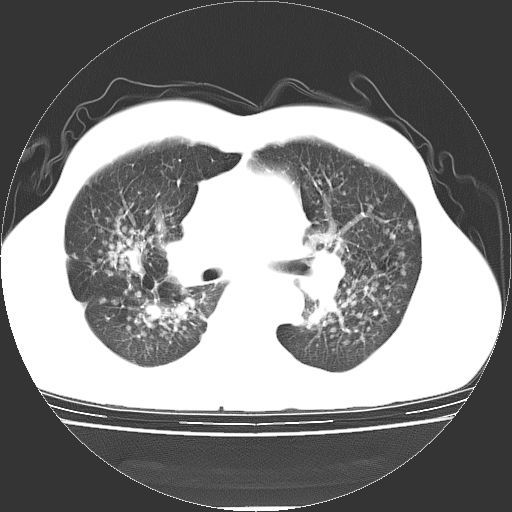

以下是引用yangyudong333在2008-4-29 5:38:00的发言:[br]比较典型的矽肺结节.支持[br]诊断依据:[br] 1.x线表现:[br] ①典型矽肺为多发直径 1~3mm 小结节,即矽结节,由胶原纤维和硅尘构成,可融合成团块,好发于上肺。[br] ②团块周围常有肺大泡。[br] ③胸内淋巴结增大、钙化。如肺门淋巴结呈蛋壳样钙化有助于与其他尘肺区别。[br] ④胸膜常广泛粘连、增厚。[br] 2.ct表现[br] ①两肺散在大小较为一致的小结节影,其密度较高,边界清楚。[br] ②小结节可融合为较大团块影,直径约 1cm ,甚至可达 10cm以上,易发生在上叶。[br] ③小结节周围常并有小叶中心气肿或弥漫性肺气肿。

以下是引用liuyue在2008-4-28 22:30:00的发言:[br]比较典型的矽肺结节.[br]请结合临床及化验除外矽肺合并肺结核之可能.